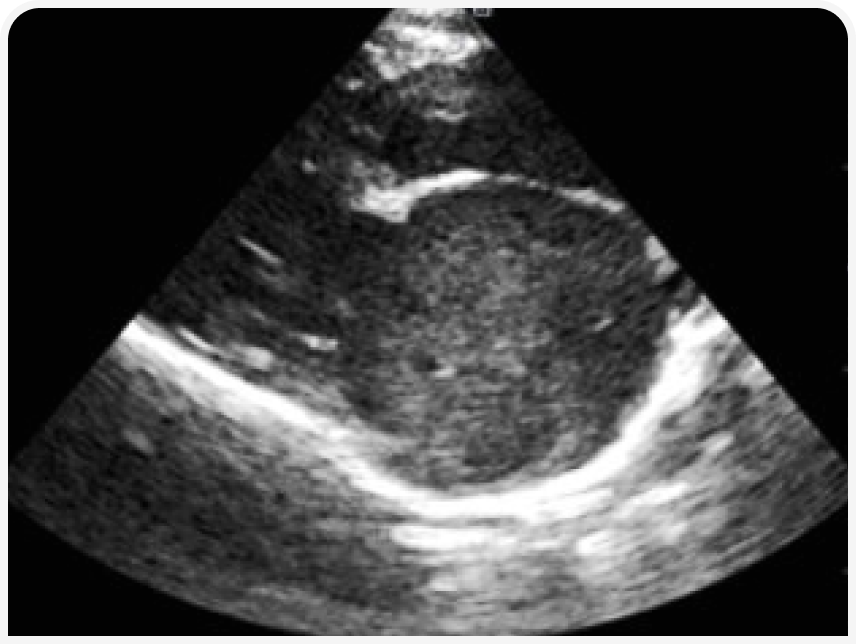

Эхокардиография (рис. 3–5). Данный метод позволяет выявить основное заболевание сердца. Также можно выявить изменение кровотока и замедленное прохождение крови в ушке или в полости левого предсердия посредством импульсно-волнового доплера. У некоторых кошек тромб, формирующийся (в виде облака) или зрелый, можно увидеть в левом предсердии.